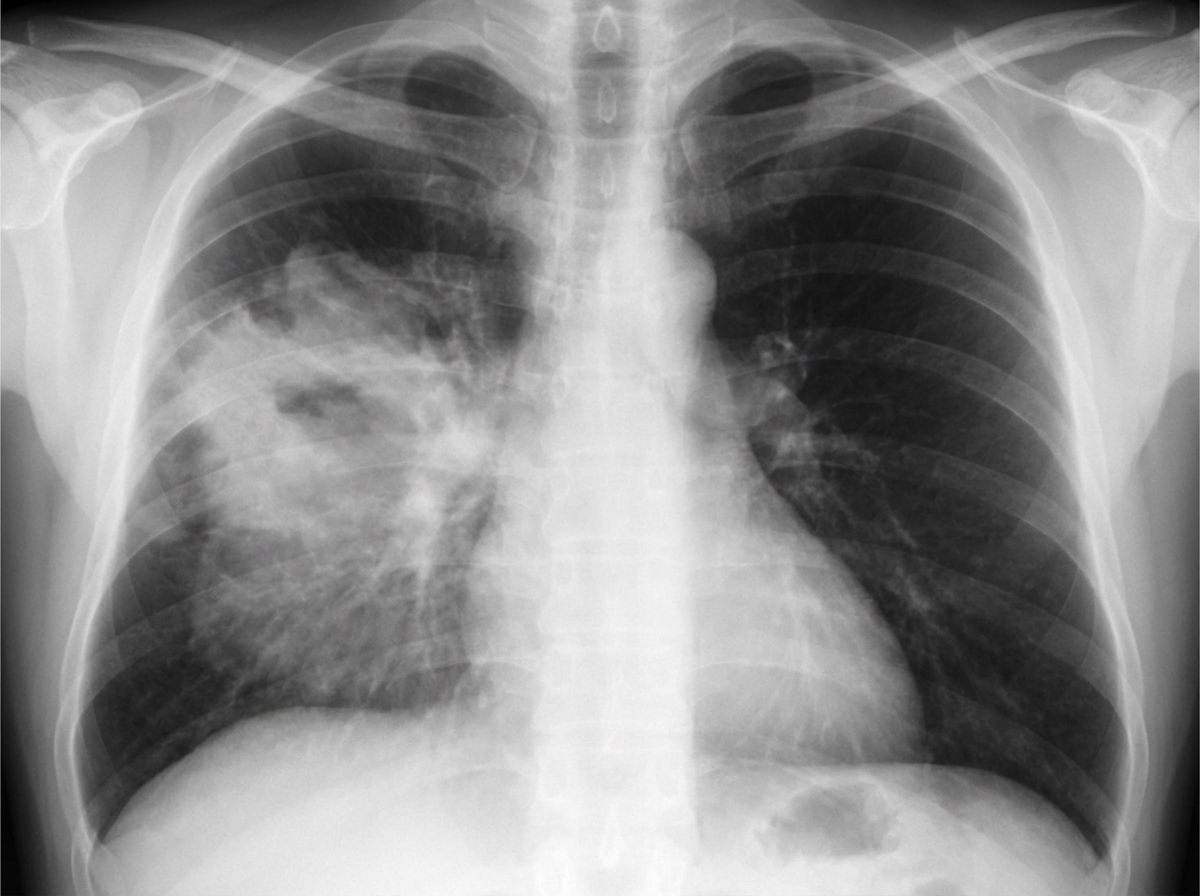

A 44-year-old man presents with dyspnea, cough, and mild pyrexia. Which lobe of the lung is most likely involved?

Explanation: ***Right middle lobe*** - The **right middle lobe** is most commonly affected in pneumonia presenting with dyspnea, cough, and pyrexia, often showing **silhouette sign** with obliteration of the **right heart border** on chest X-ray. - On **lateral chest X-ray**, right middle lobe consolidation appears as opacity in the **anterior-inferior portion** of the thorax, helping differentiate from other lobes. *Right upper lobe* - Right upper lobe pneumonia typically shows consolidation **above the horizontal fissure** and would obliterate the **right paratracheal stripe**, not the heart border. - On lateral view, opacity would be located in the **anterior-superior** portion, distinctly different from middle lobe involvement. *Left lower lobe* - Left lower lobe consolidation would obliterate the **left hemidiaphragm** and **descending aorta** silhouette, not affecting the right heart border. - Symptoms would be similar, but radiological findings show **retrocardiac opacity** on PA view and **posterior-inferior** opacity on lateral view. *Left upper lobe* - Left upper lobe pneumonia would cause loss of the **left heart border** and **aortic knob** silhouette, with opacity in the **upper left thorax**. - On lateral chest X-ray, consolidation appears in the **anterior-superior** region, similar to right upper lobe but on the opposite side.